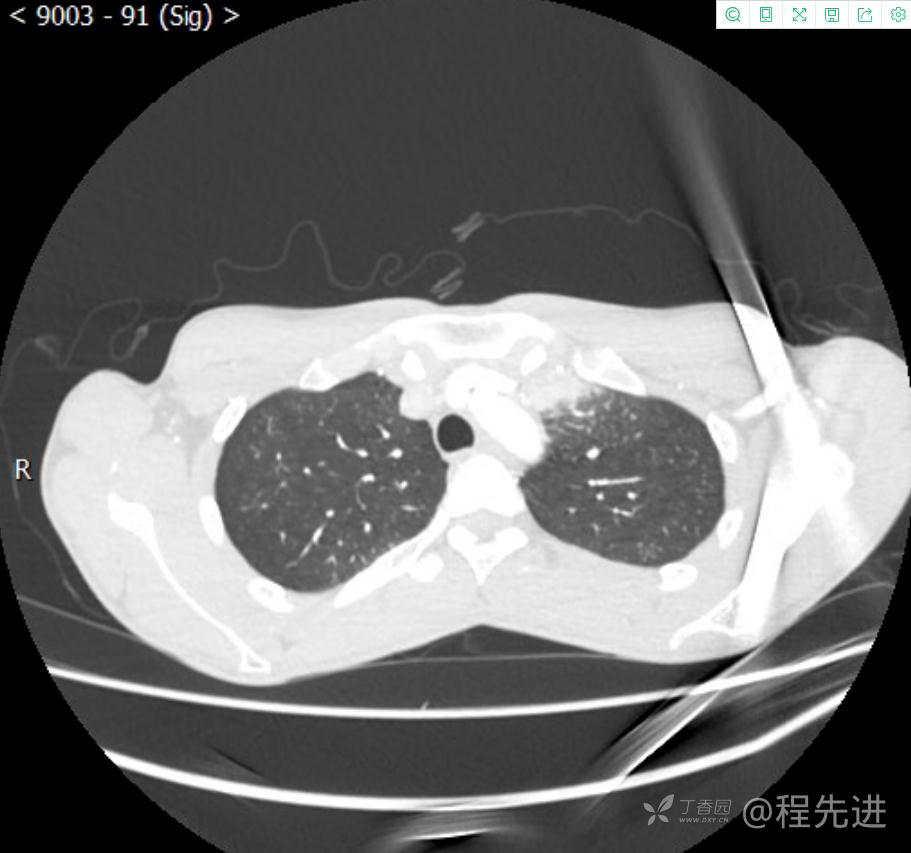

主诉:反复咳嗽1月,发现“纵隔”占位半月,乏力10余天。

现病史:患者1月前无明显诱因出现咳嗽,以夜间为著,伴有少量白痰,无发热,无胸痛、咯血,无痰中带血,未予重视,半月前外院行胸部CT检查发现“左前上纵隔”占位,未予进一步检查及治疗。近10余天自觉乏力,逐渐加重。